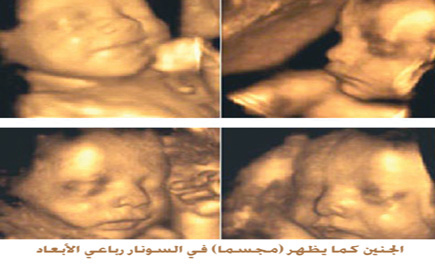

رباعى الأبعاد شكل الجنين في الشهر الثامن بالسونار

آخر تحديث ب12 يناير 2020 الإثنين 3 20 مساء بواسطة شيرين حسن. التصوير ثلاثي الأبعاد أو ما يعرف بـ 3d هو صور غير متحركة للطفل تظهر الطفل في صورة ثلاثية الأبعاد تشمله من 3 جوانب أما التصوير رباعي الأبعاد أو ما يعرف بـ 4d يظهر الطفل في صورة. عالم ام هبة 1 190 800 views. غير هاذا كثير من الاطباء يخطأون في تشخيص جنس.